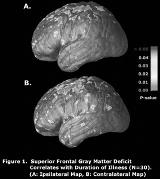

There is emerging evidence that patients with mesial temporal lobe epilepsy (MTLE) and hippocampal sclerosis (HS) have structural abnormalities that extend beyond the hippocampus. We report on a quantitative volumetric MRI study of patients with pathologically confirmed HS. Gray and white matter deficits were correlated with clinical variables. Quantitative volumetric analyses were performed on preoperative MRI brain scans of 15 left and 15 right MTLE (LMTLE/RMTLE) patients who underwent anteromesial temporal resection and have been seizure free for at least 2 years, and 20 age matched normal controls. MRI images were linearly registered to the International Consortium for Brain Mapping (ICBM) space. Tissue were classified into gray matter, white matter and cerebrospinal fluid. Lobar and whole hemisphere gray and white matter volumes were compared to normal controls. Regression analyses were performed to correlate tissue volumes with age, seizure duration, and history of febrile seizures. In LMTLE patients, a 35.6% average gray matter deficit was found in the left and a 34.6% average deficit in the right hemisphere (both P[lt].0001). In the RMTLE patients, a 39.4% gray matter deficit was found in the left and 40.4% in the right hemisphere (both P[lt].0001). There also was significant white matter loss in both MTLE groups with maximal deficit in the frontal and temporal lobes. Regression analysis showed that the age of the patient and duration of seizures were negatively correlated with gray matter volume ipsilateral (P[lt].04) and contralateral (P[lt].05) to the side of seizure onset. A history of febrile seizures did not correlate with tissue volumes. When data from the affected hemispheres of both MTLE groups were pooled, cortical gray matter deficits in superior frontal regions correlated significantly with seizure duration (P[lt].05, permutation test). Quantitative volumetric analysis of MTLE with HS showed widespread deficits in gray and white matter. Gray matter loss in superior frontal regions correlated with age and duration of seizures. This suggests MTLE may be a progressive disease involving multiple specific brain regions outside of the temporal lobe.[figure1] (Supported by Epilepsy Foundation and National Epifellows Foundation)